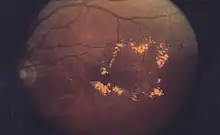

Cystoid macular edema (CME) involves fluid accumulation in the outer plexiform layer secondary to abnormal perifoveal retinal capillary permeability. The edema is termed "cystoid" as it appears cystic; however, lacking an epithelial coating, it is not truly cystic. The cause for CME can be remembered with the mnemonic "DEPRIVEN" (diabetes, epinepherine, pars planitis, retinitis pigmentosa, Irvine-Gass syndrome, venous occlusion, E2-prostaglandin analogues, nicotinic acid/niacin).